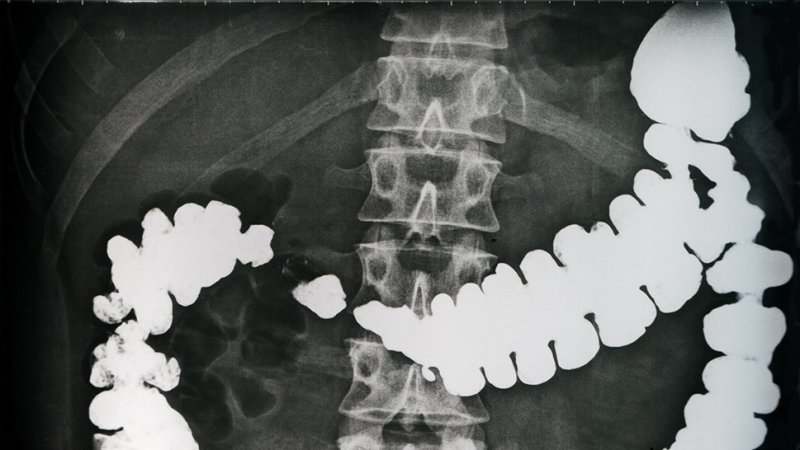

Prior to examination by computer tomography, the doctor administers a contrast medium solution to the patient.